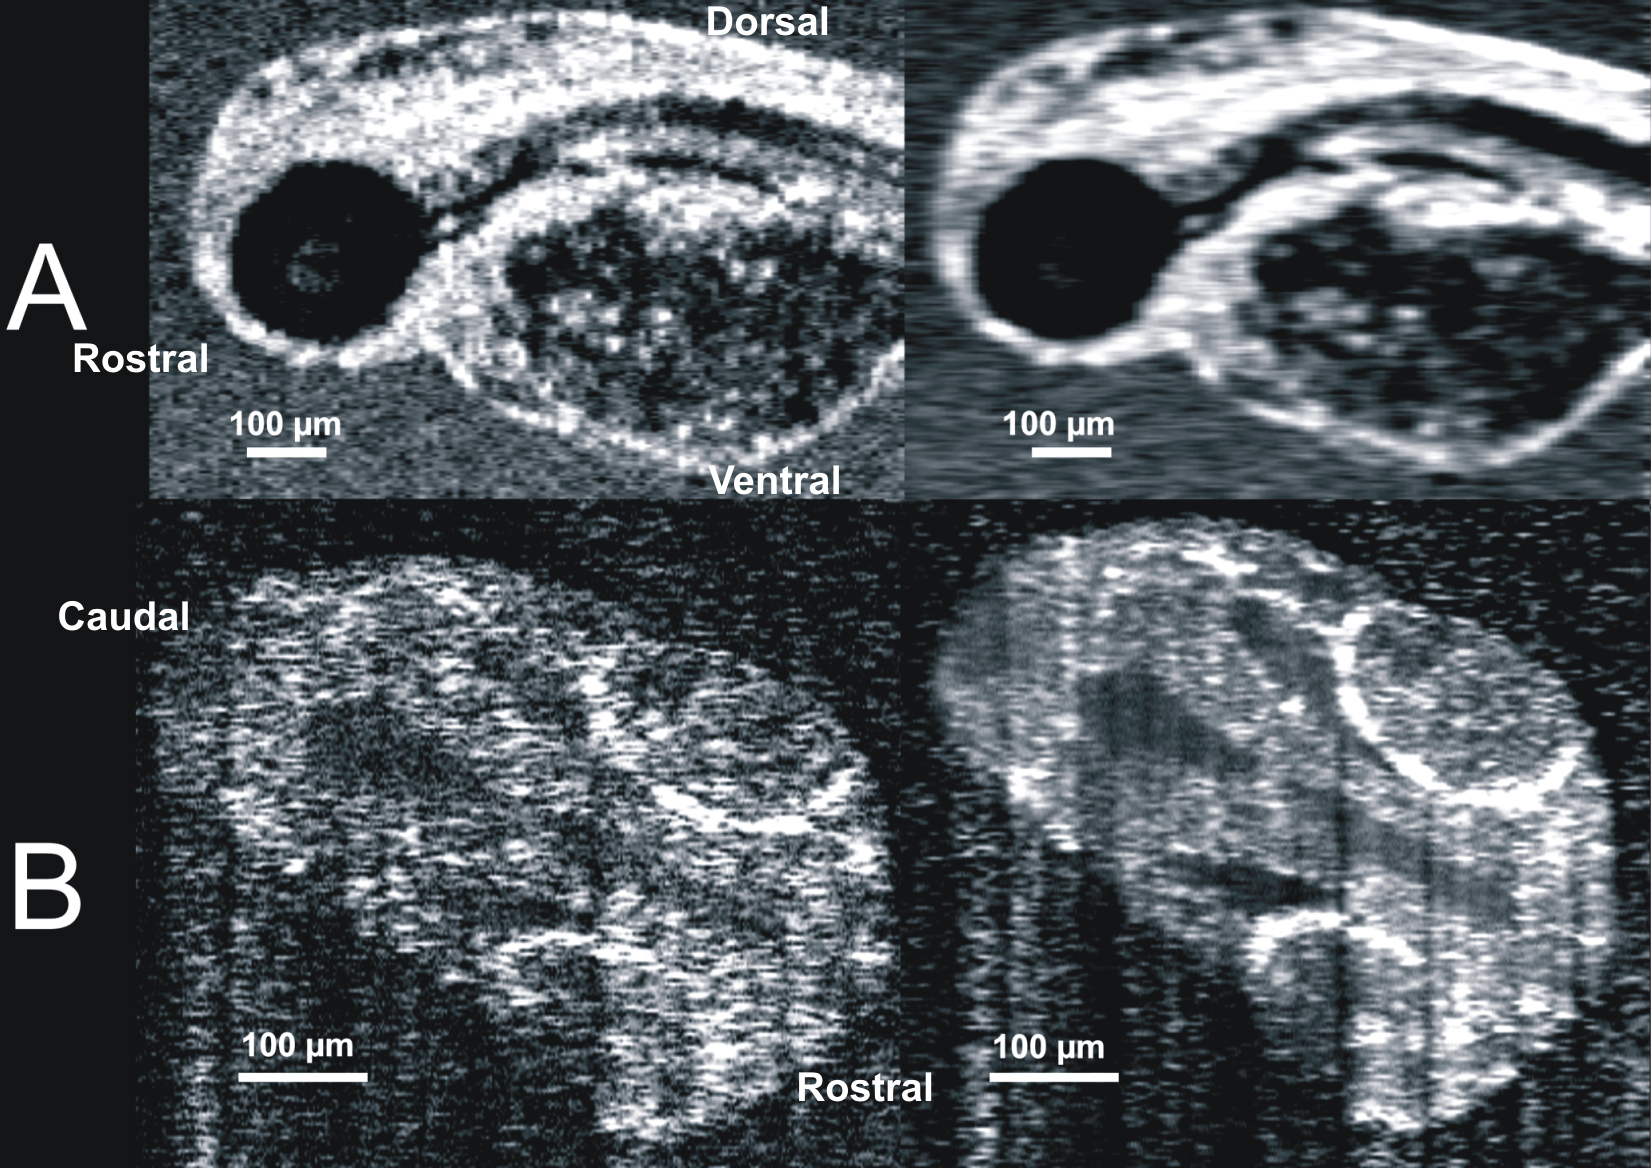

Figure 3. Data averaging reduces noise and

enhances contrast between structures. A: A rolling 3-frame

average within a 120 h post fertilization (hpf) embryo improves

visualization of soft tissue structures in the gut while blurring the

sharp features of the eye and ear. B: A side by side comparison

of a single frame and a 120 frame averaged within the brain of a 24 hpf

embryo demonstrates that aggressive averaging of repeated line scans

increased visualization of soft tissue features and reduced noise.